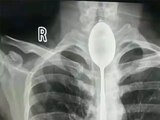

El hijo de Gauthier sugirió que quizás su padre se había tragado el audífono, que es exactamente lo que reveló una radiografía en una clínica de emergencia local. El pequeño audífono inalámbrico estaba alojado en la parte inferior de su esófago.